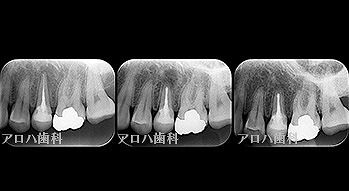

case10

左上に腫脹、圧痛

根尖部に透過像

術前、術直後、予後

術前、術後